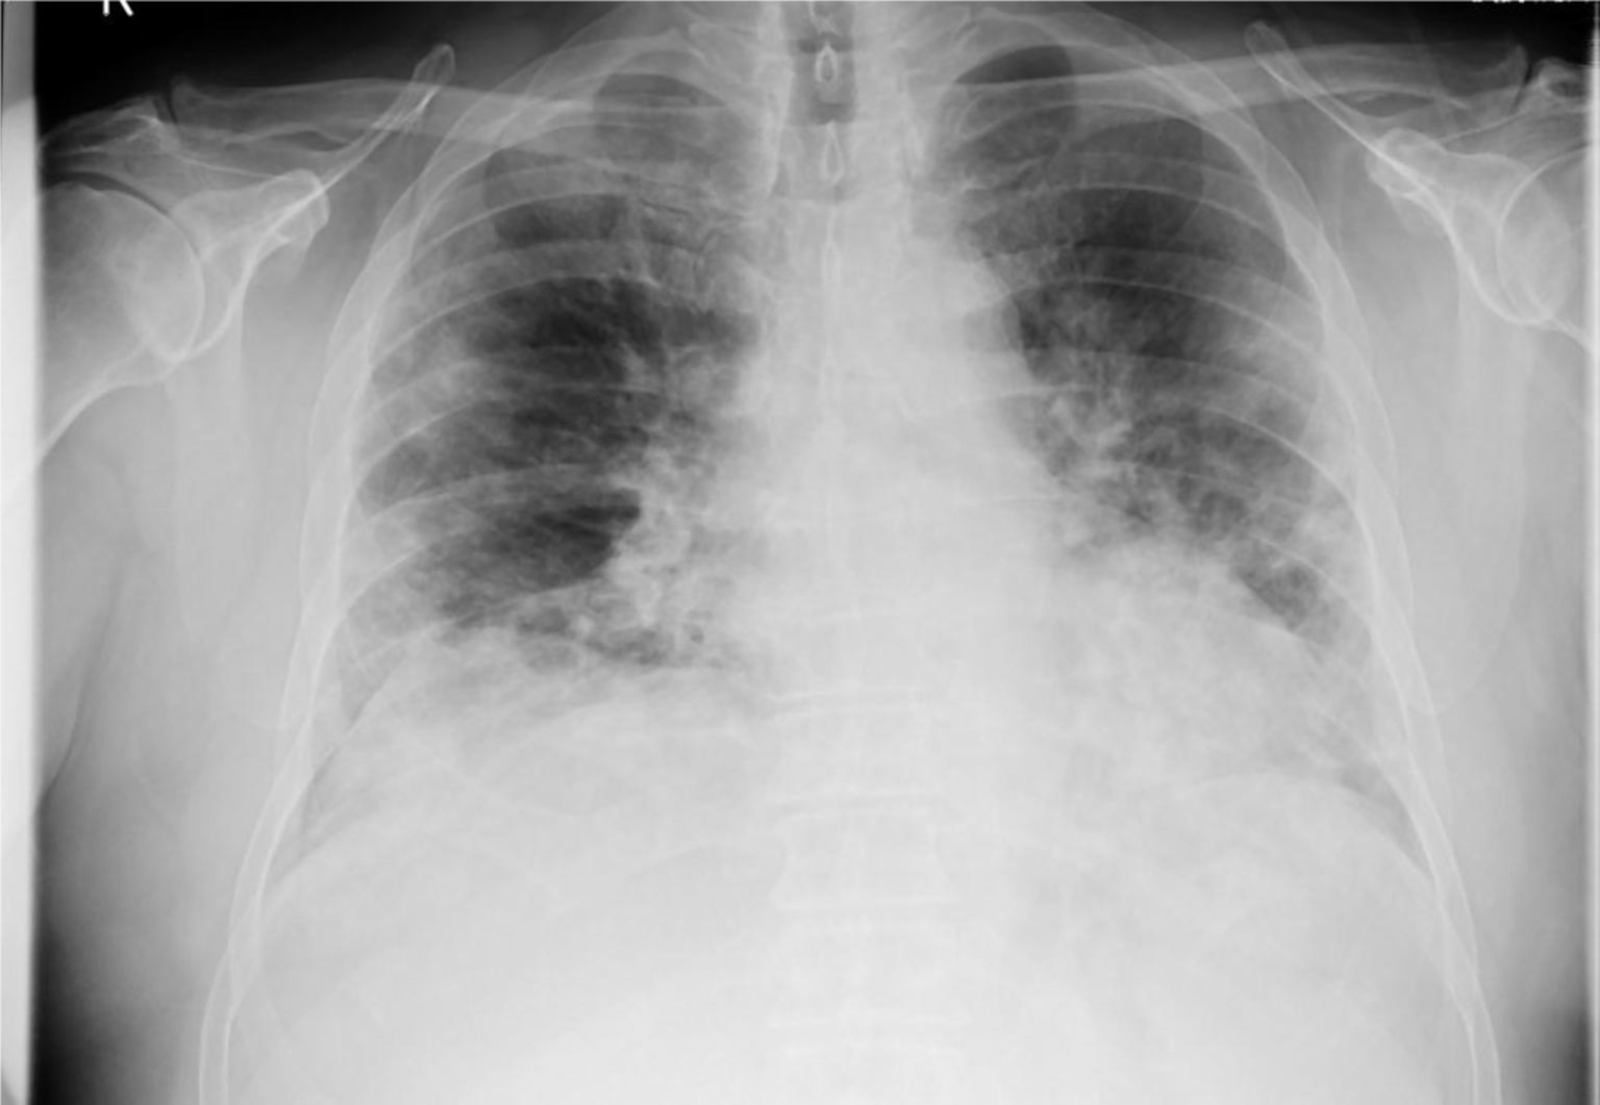

Bei ihrer Arbeit wurde Kopp von ihrem Professor Dr. Alexander Jesser unterstützt. „Bei einer Erkrankung der Lunge ist das betroffene Gewebe meist weniger transparent für die Röntgenstrahlung und kann durch seine Form und Abgrenzung Aufschluss geben, um welche Art der Krankheit es sich handelt. Eine Covid-19-Erkrankung zeigt meist milchglasartige Veränderungen in beiden Lungenflügeln. Ist eine Erkrankung der Lunge durch eine Infektion mit Bakterien erfolgt, ist mehrheitlich nur ein Flügel der Lunge verändert. Eine gleichmäßige Ausbreitung über alle Bereiche der Lunge ist dabei also ein Hinweis auf eine Covid-19 Infektion“, erläutert Jesser.

Damit die Aufnahmen vom Programm ausgewertet werden können, müssen sie in einen Standard-PC eingelesen werden. Danach wird mit einer speziellen mathematischen Operation der Kontrast erhöht. Dadurch können auch qualitativ schlechtere Aufnahmen analysiert werden, die häufig durch ältere Geräte zu Stande kommen. Neben dem Falschfarbenbild erstellt die Software ein sogenanntes „Binärbild“, auf welchem sich bereits die Umrisse der Lunge, sowie Spuren von geschädigtem Gewebe erkennen lassen.

Mithilfe eines weiteren Algorithmus werden die dort vorhandenen Kanten und Grenzen der einzelnen Bereiche ermittelt. Durch weitere Berechnungen werden Flächen- und Symmetriebetrachtungen vollzogen. Dadurch soll letztlich mit großer Wahrscheinlichkeit zwischen bakterieller oder viraler Lungenentzündung unterschieden werden. Dr. Konrad Appelt, Radiologe am Universitätsspital Basel, verweist ebenfalls auf den Nutzen der Software: „Klar ist, dass durch diese Methode ein qualifizierter Arzt nicht ersetzt werden kann und ein einfaches Röntgenbild nicht die diagnostische Qualität eines Computertomographens aufweist, sie kann aber eine sehr sinnvolle, zusätzliche Maßnahme zur Diagnose der Covid-19 Erkrankung sein.“